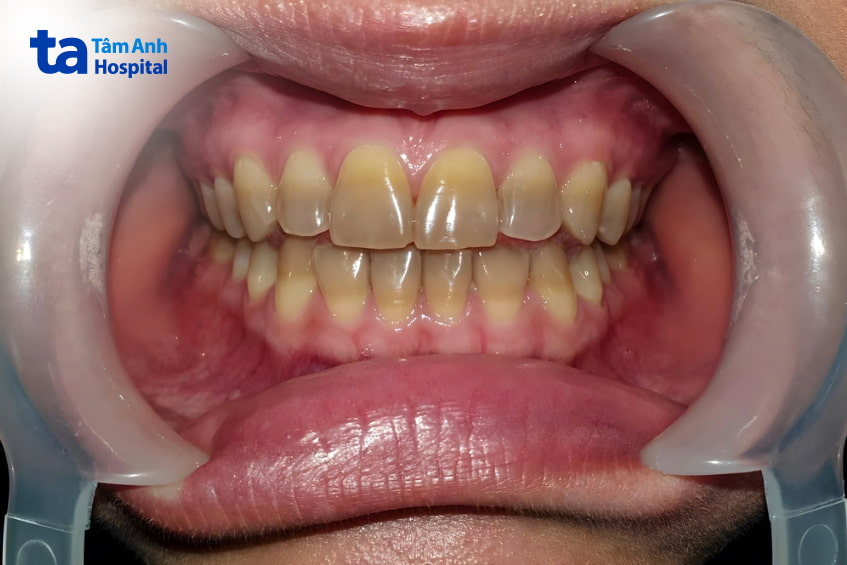

Răng nhiễm tetracycline là tình trạng răng đổi màu do kháng sinh nhóm tetracycline. Khi nhiễm tetracycline, răng có thể chuyển thành nhiều màu như vàng, xanh lá, xanh dương, đỏ, nâu, xám, thậm chí màu đen. Màu sắc răng ảnh hưởng bởi loại thuốc, mức độ, thời gian dùng tetracycline.

Triệu chứng thường thấy nhất của răng nhiễm tetracycline là màu răng thay đổi thành vàng, nâu, đỏ, xanh, đen,… tùy theo mức độ nhiễm màu. Răng mới mọc của trẻ nhiễm tetracycline có màu vàng và đổi màu sau khi tiếp xúc với ánh sáng mặt trời. Do đó, răng hàm phía trong thường không đậm màu bằng những răng phía trước hàm.

Răng đổi màu do nhiễm tetracycline là tình trạng vĩnh viễn và thường nặng hơn theo thời gian. Ngoài ra, răng nhiễm tetracycline có thể phát sáng dưới ánh sáng cực tím trong phòng tối. Bên cạnh đổi màu, men răng cũng suy yếu, khiến răng dễ sâu, nứt, bể,… hoặc mắc các bệnh răng miệng hơn.